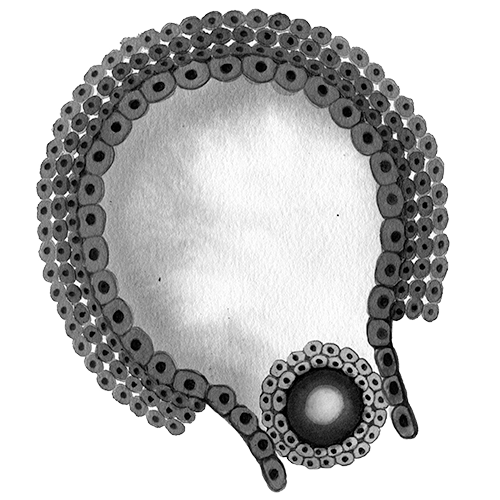

How an egg retrieval works

She wasn’t the ideal candidate. Donors over 35 are considered geriatric, and the cousin was 36. A woman has as many as 2 million eggs at birth, but by her mid- to late 30s, fewer than 3% remain.

Around that time, researchers began experimenting with freezing eggs. Success rates were low. The human egg is 90% water, and when it freezes, ice crystals can damage the delicate spindle of chromosomes inside. Even as IVF became mainstream, only a few births using frozen eggs occurred over the next two decades.

By the early 2000s a new technology, known as vitrification, allowed eggs to be frozen so quickly that the fluid has no time to form crystals and instead turns into a glasslike solid. In 2012 two of the world’s largest organizations representing fertility practitioners backed the technique. Vitrification boomed. In the US alone, the number of fertility procedures using frozen donor eggs or embryos tripled from 2012 to 2021, to 26,700, according to the Centers for Disease Control and Prevention.